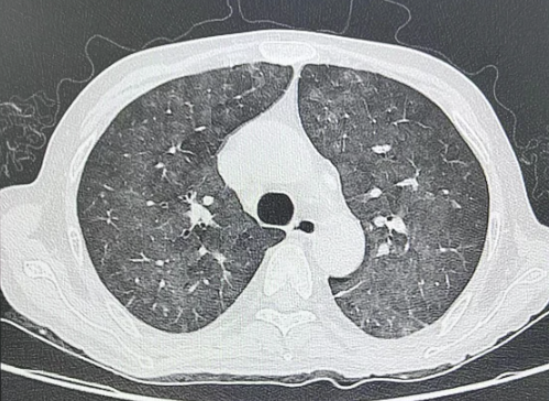

临床表现: 50岁男性,肾移植术后,免疫抑制状态。出现高热、呼吸困难、低氧血症。CT示双肺弥漫性磨玻璃影,G实验:>600pg/ml。

肺CT示:两肺间质纹理增多,两肺弥漫磨玻璃密度影及索条影较前增多,部分密度增高。考虑两肺感染性病变

mNGS报告(肺泡灌洗液): 耶氏肺孢子菌(序列数:454),口腔链球菌群(序列数:4530),奈瑟菌属(低序列)。

报告解读: 在免疫抑制患者中,耶氏肺孢子菌即使序列数不高也需高度重视,它往往是“低调的真凶”。而口腔菌群是BALF的“常客”。此时,报告的核心价值在于揪出了耶氏肺孢子菌。

临床决策与结局: 立即启用复方磺胺甲噁唑治疗,患者病情逐步稳定。但是肺孢子菌并非检出均是感染病原,其可为定植,例如新生儿,肺孢子菌定植常见,检出≠感染。结论: 同一微生物,在不同宿主背景下,其临床意义天差地别。宿主因素是解读报告的基石!